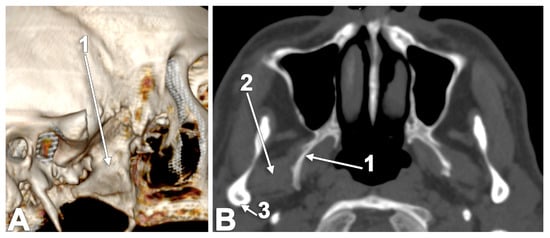

5.1. Broad Lateral Pterygoid Plates

5.2. The Pterygospinous and Pterygoalar Bars